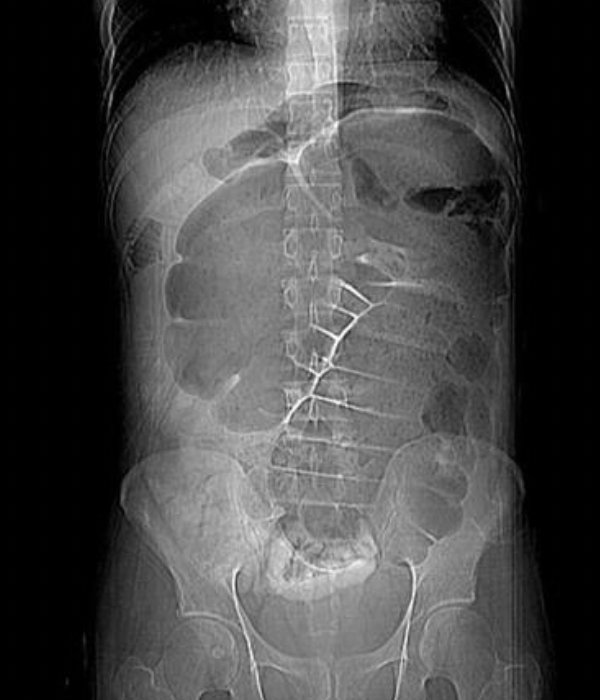

Sigmoid volvulus

Coffee bean sign